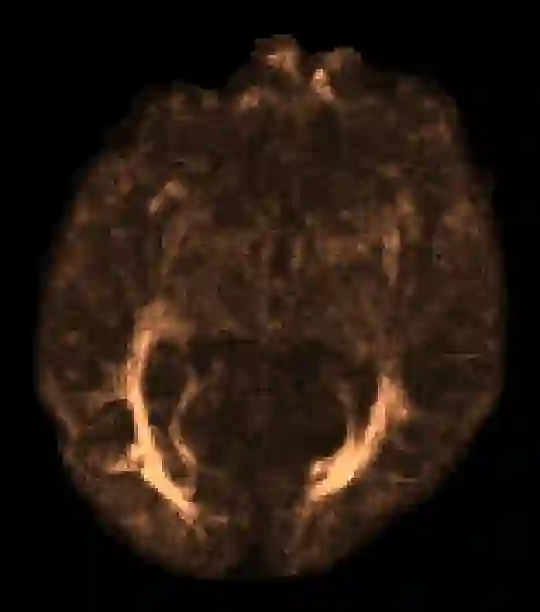

In machine learning, novelty detection is the task of identifying novel unseen data. During training, only samples from the normal class are available. Test samples are classified as normal or abnormal by assignment of a novelty score. Here we propose novelty detection methods based on training variational autoencoders (VAEs) on normal data. Since abnormal samples are not used during training, we define novelty metrics based on the (partially complementary) assumptions that the VAE is less capable of reconstructing abnormal samples well; that abnormal samples more strongly violate the VAE regularizer; and that abnormal samples differ from normal samples not only in input-feature space, but also in the VAE latent space and VAE output. These approaches, combined with various possibilities of using (e.g. sampling) the probabilistic VAE to obtain scalar novelty scores, yield a large family of methods. We apply these methods to magnetic resonance imaging, namely to the detection of diffusion-space (q-space) abnormalities in diffusion MRI scans of multiple sclerosis patients, i.e. to detect multiple sclerosis lesions without using any lesion labels for training. Many of our methods outperform previously proposed q-space novelty detection methods. We also evaluate the proposed methods on the MNIST handwritten digits dataset and show that many of them are able to outperform the state of the art.